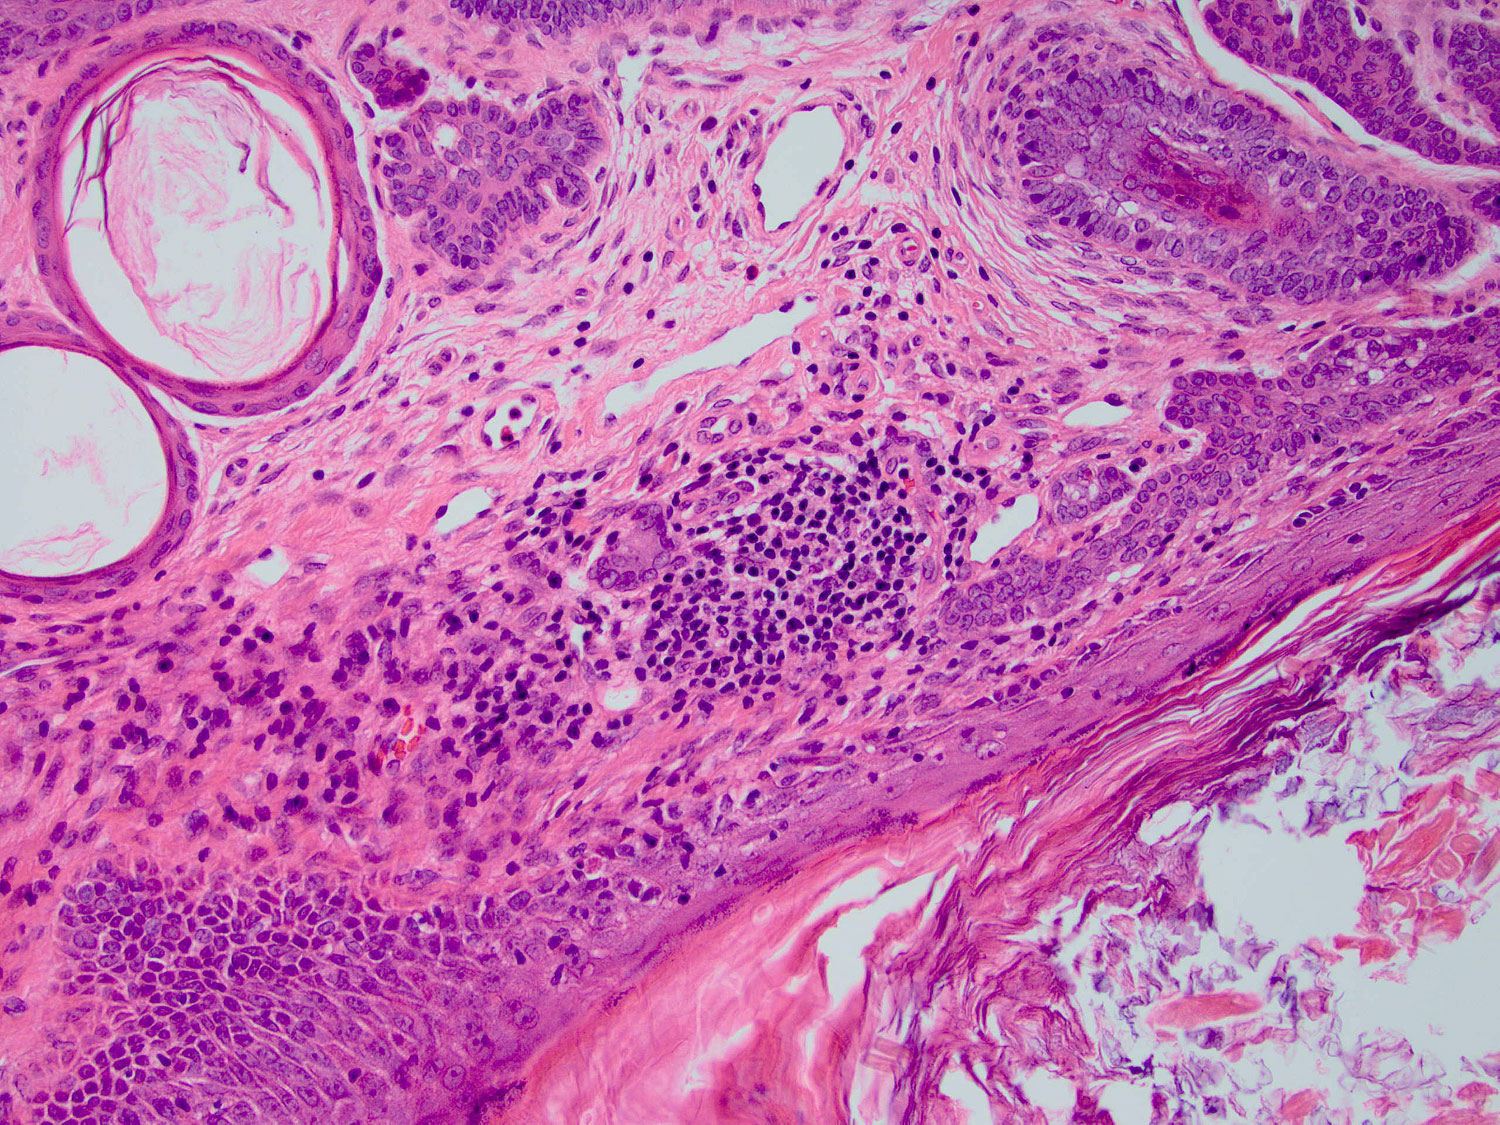

Granulomatous inflammation

H&E staining (20x objective)